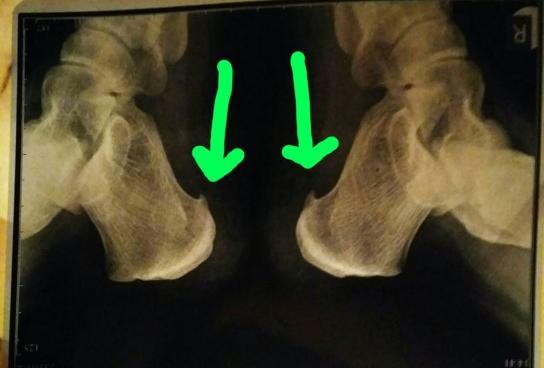

Блокада пяточной шпоры Дипроспаном - лечебная процедура, предусматривает введение гормонального средства в комплексе с анестетиком непосредственно в зону поражения . Укол делают прямо в пятку, благодаря чему происходит выключение болевого рефлекса, а также . . .

Блокады делают с применением лекарств с выраженным противовоспалительным и обезболивающим эффектом - глюкокортикоидов . Техника проведения Блокада пятки Дипроспаном выполняется только врачом . Необходимо четкое соблюдение техники проведения и дозировки препаратов, поэтому процедуру делает квалифицированный специалист, чаще ортопед-травматолог .

Процедура блокады пяточной шпоры . Анестетик зачастую не используется при блокировке, а если и применяется, то изначально набирается 0,5 мл Дипроспана, Кеналога или Гидрокортизона, потом добавляется раствор Лидокаина 1% и, встряхивая, перемешивается . Область внедрения . . .

Для блокады пяточной шпоры используют кеналог, дипроспан, гидрокортизон . Дипроспан считается самым эффективным лекарственным препаратом, так как действующее вещество бетаметазона динатрия фосфат легко растворяется, быстро всасывается и долго сохраняется в очаге воспаления .